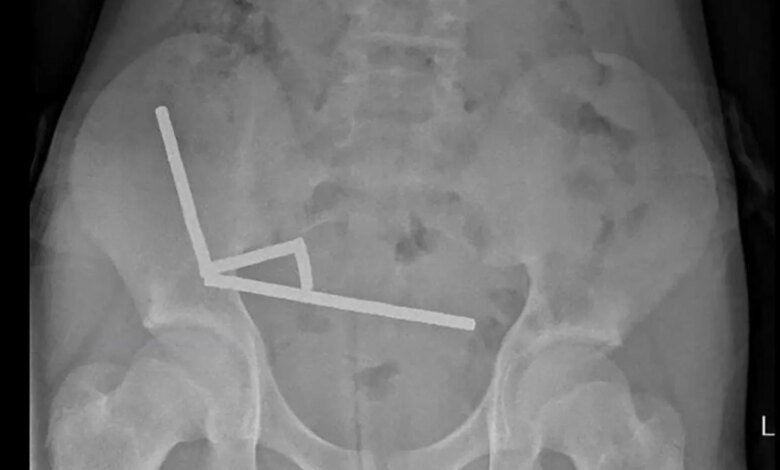

Researchers said an X-ray was taken and showed “four linear chains of magnets” linked together, composed of what the boy indicated was “approximately 80–100 5x2mm high-power (neodymium) magnets” that he allegedly purchased from online retailer Temu.

Photos published in the study showed the retrieval process, and indicated that the magnets “appeared to be in separate parts of bowel” but were “adhered together due to magnetic forces.”